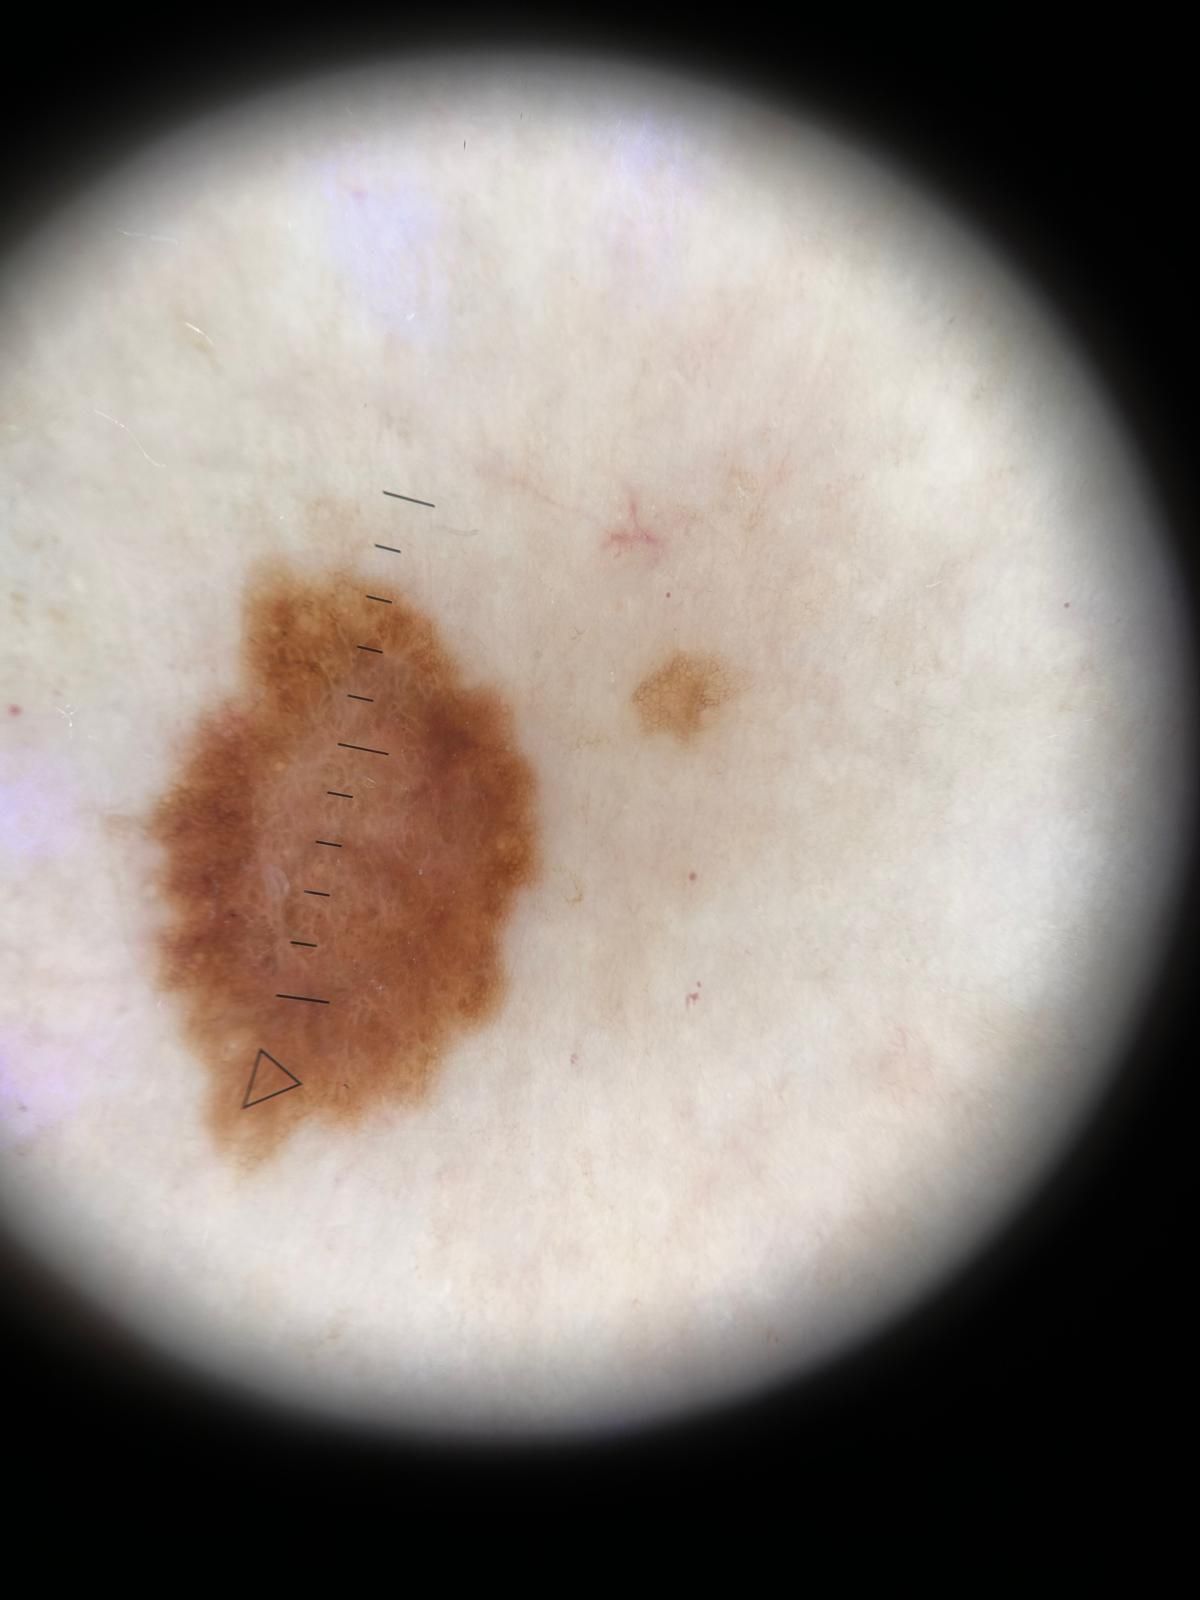

Con esperienza ventennale, attualmente esercita in libera professione presso Studio Medico sito in Via Domenico di Marco 5 B a Palermo, e in Via Piersanti Mattarella 13 C Termini Imerese, occupandosi in particolare di diagnosi precoce di Melanoma attraverso videodermatoscopia digitale, Mappatura delle lesioni melanocitarie, crioterapia.

• Dermatoscopia

100 €

• Osservazione dermatologica in epiluminescenza